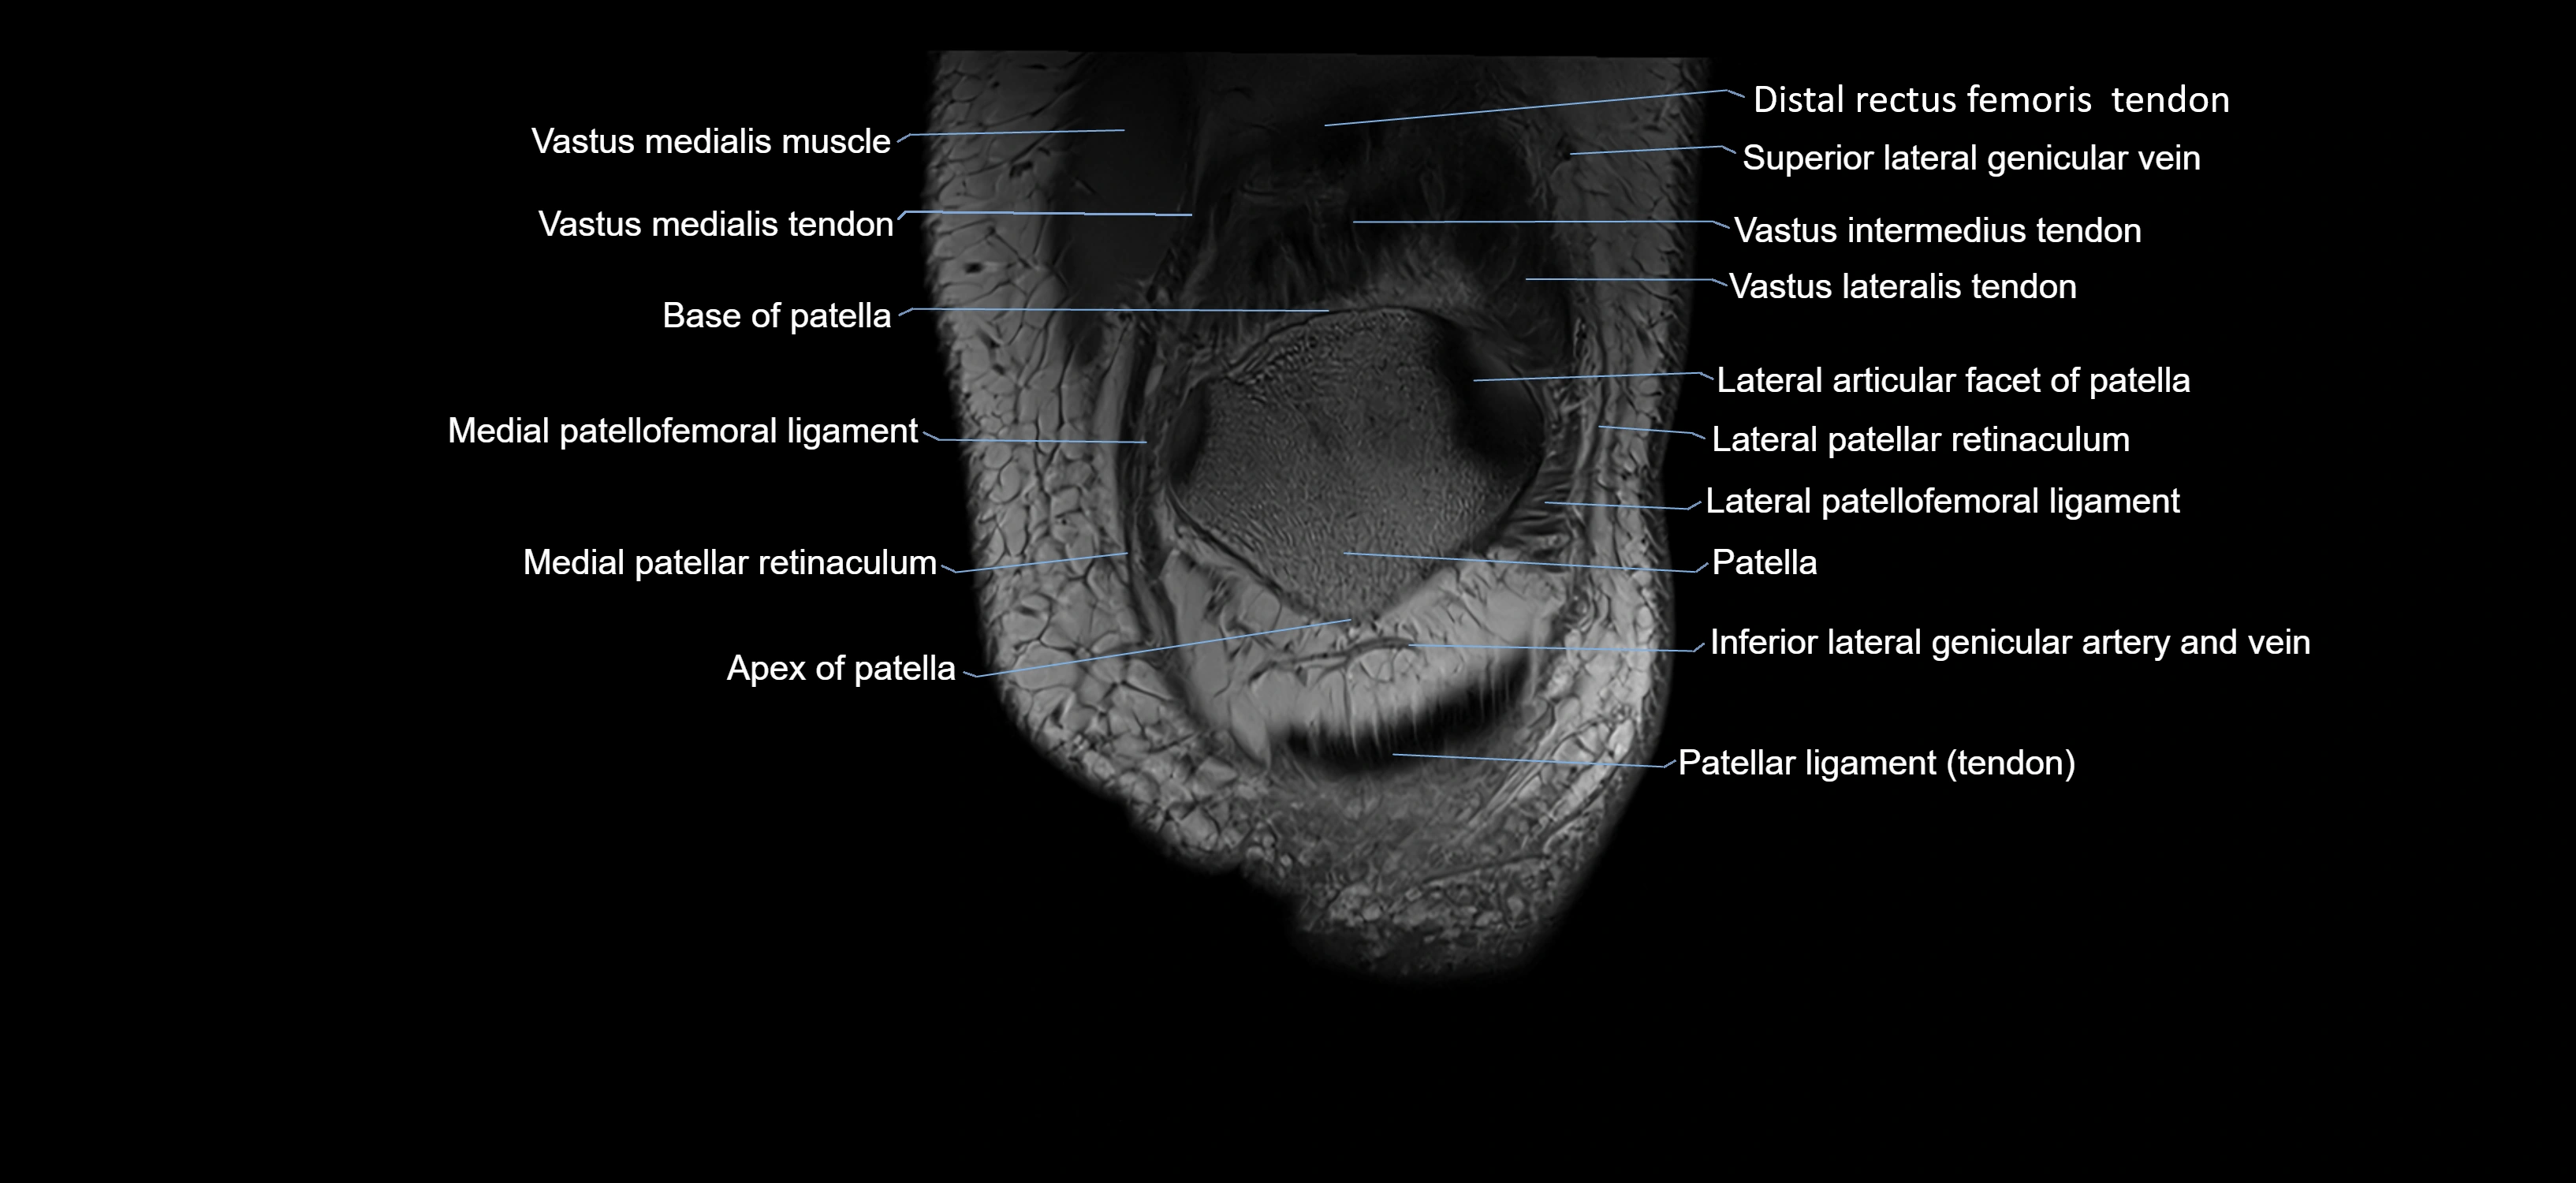

- Apex of patella

- Base of patella

- Distal rectus femoris tendon

- Distal vastus intermedius tendon

- Distal vastus lateralis tendon

- Distal vastus medialis tendon

- Inferior lateral genicular artery

- Inferior lateral genicular vein

- Lateral articular facet of patella

- Lateral patellar retinaculum

- Lateral patellofemoral ligament

- Medial patellar retinaculum

- Medial patellofemoral ligament

- Patella

- Patellar tendon (patellar ligament)

- Superior lateral genicular vein